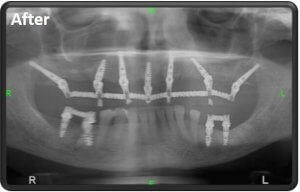

Невинтовые имплантаты, предназначенные для отсутствия кости в верхней и нижней челюстях. Эти имплантаты имеют дискообразную головку и прикреплены к челюсти по бокам дёсен в областях, где отсутствует челюстная кость. В отличие от скуловых имплантатов, дисковые имплантаты не могут удерживать мост сами по себе, а требуют размещения обычных имплантатов в областях, где плотность кости достаточно высока для того, чтобы их закрепить.

השתלת שיניים בזאלית